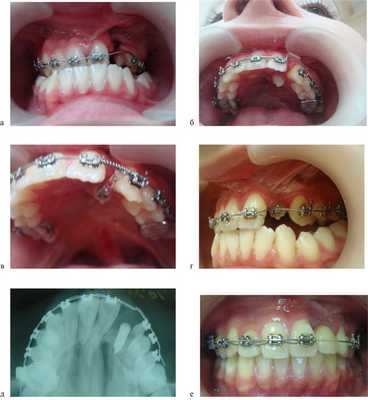

По окончании периода ретенции ортодонтическое лечение было направлено на нормализацию положения зубов, формирование оптимальной окклюзии (рис. 5, а—г).

Рис. 5. Этапы ортодонтического лечения по окончании периода ретенции. а — до костной пластики; б—г — перемещение небно расположенного бокового резца в костный регенерат; д, е — имплантат в области костного регенерата.

При адентии бокового резца в область костного регенерата вводили имплантат (см. рис. 5, д, е).